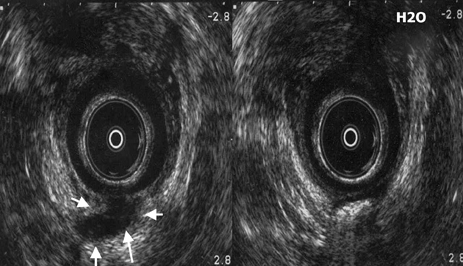

Imágenes de un mismo paciente correspondientes a fístula supraesfinteriana. Izquierda: zona hipoecogénica posterior a nivel del puborrectal correspondiente al trayecto de la fístula (flechas). Derecha: con H2O2 se confirma que se rellena el trayecto con agua oxigenada y se hace hiperecogénico y deja sombra posterior. |